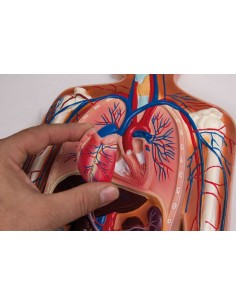

3B Scientific, Torse bisexuel, modèle de luxe, séparable en 20 parties B32

3B Scientific, Torse bisexuel, modèle de luxe, séparable en 20 parties B32

3B Scientific, mini torse humain sans tête, décomposable en 9 parties B20